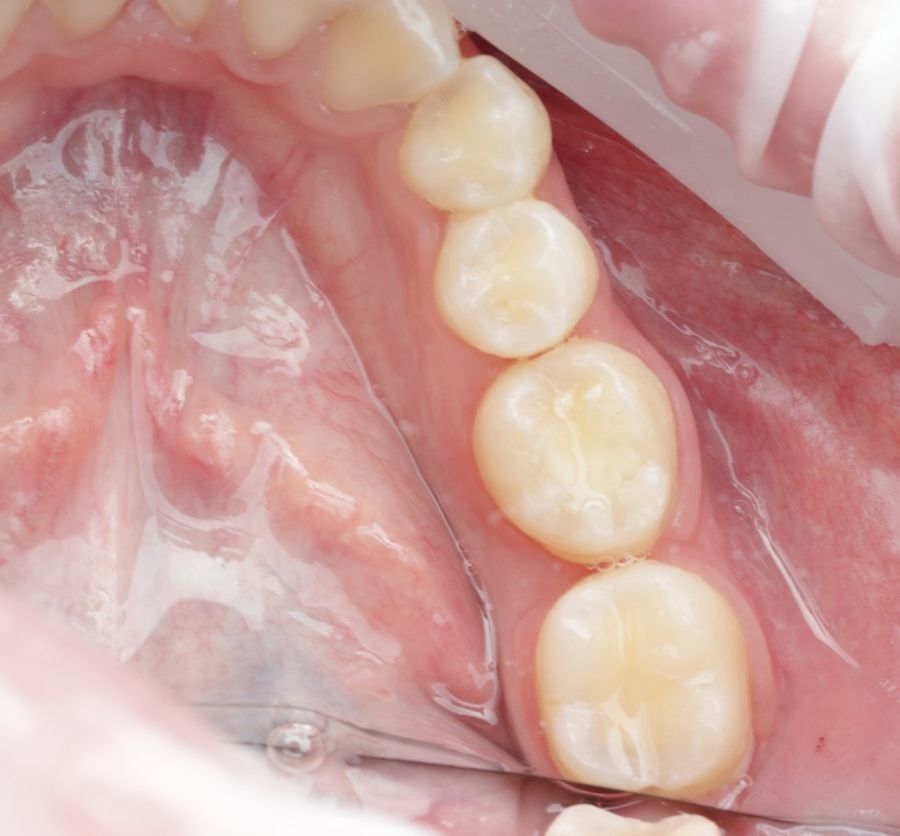

Se reporta el caso de un autotrasplante del tercer molar inferior derecho al alveolo postextracción de un primer molar inferior, en una paciente de 22 años de edad. Actualmente, el autotransplante se considera una opción de tratamiento si se siguen los criterios de selección del caso adecuados, y se realiza una técnica quirúrgica protocolizada. El diagnóstico planificado mediante CBCT, la simulación virtual y la confección de una réplica en 3D optimiza la técnica de forma segura, predecible con tiempos de cirugía menores.

Los dientes utilizados para realizar un AD más frecuentemente suelen ser de premolares a incisivo, de cordal a primer o segundo en pacientes jóvenes con ápice abierto. En adultos con ápice cerrado suele ser el autotransplante de cordal a primer o segundo molar3,4,6.

El diente donante ideal debería tener una anatomía radicular de fácil instrumentación endodóntica, y ápice abierto de al menos 1,5mm de diámetro para permitir una adecuada revascularización, con formación radicular de al menos 2/3. Así mismo, debería ser lo suficientemente pequeño para el asentamiento adecuado en el alveolo receptor, cónico, cuya extracción se pueda realizar de forma atraumática3,5,7.

El sitio receptor debe garantizar la adaptación del diente donante, se realizará un diagnóstico mediante planificación con CBCT que permita segmentar virtualmente el diente donante y llevarlo digitalmente al sitio receptor3.